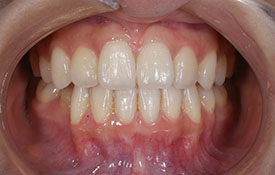

インビザラインの治療例:CASE-1

| プロフィール | 42歳 女性 |

| 所見 | 他院で行われた矯正歯科治療後の後戻りに悩まれて来院されました。 アイライナーの装着は、1日平均20時間ほどでした。 |